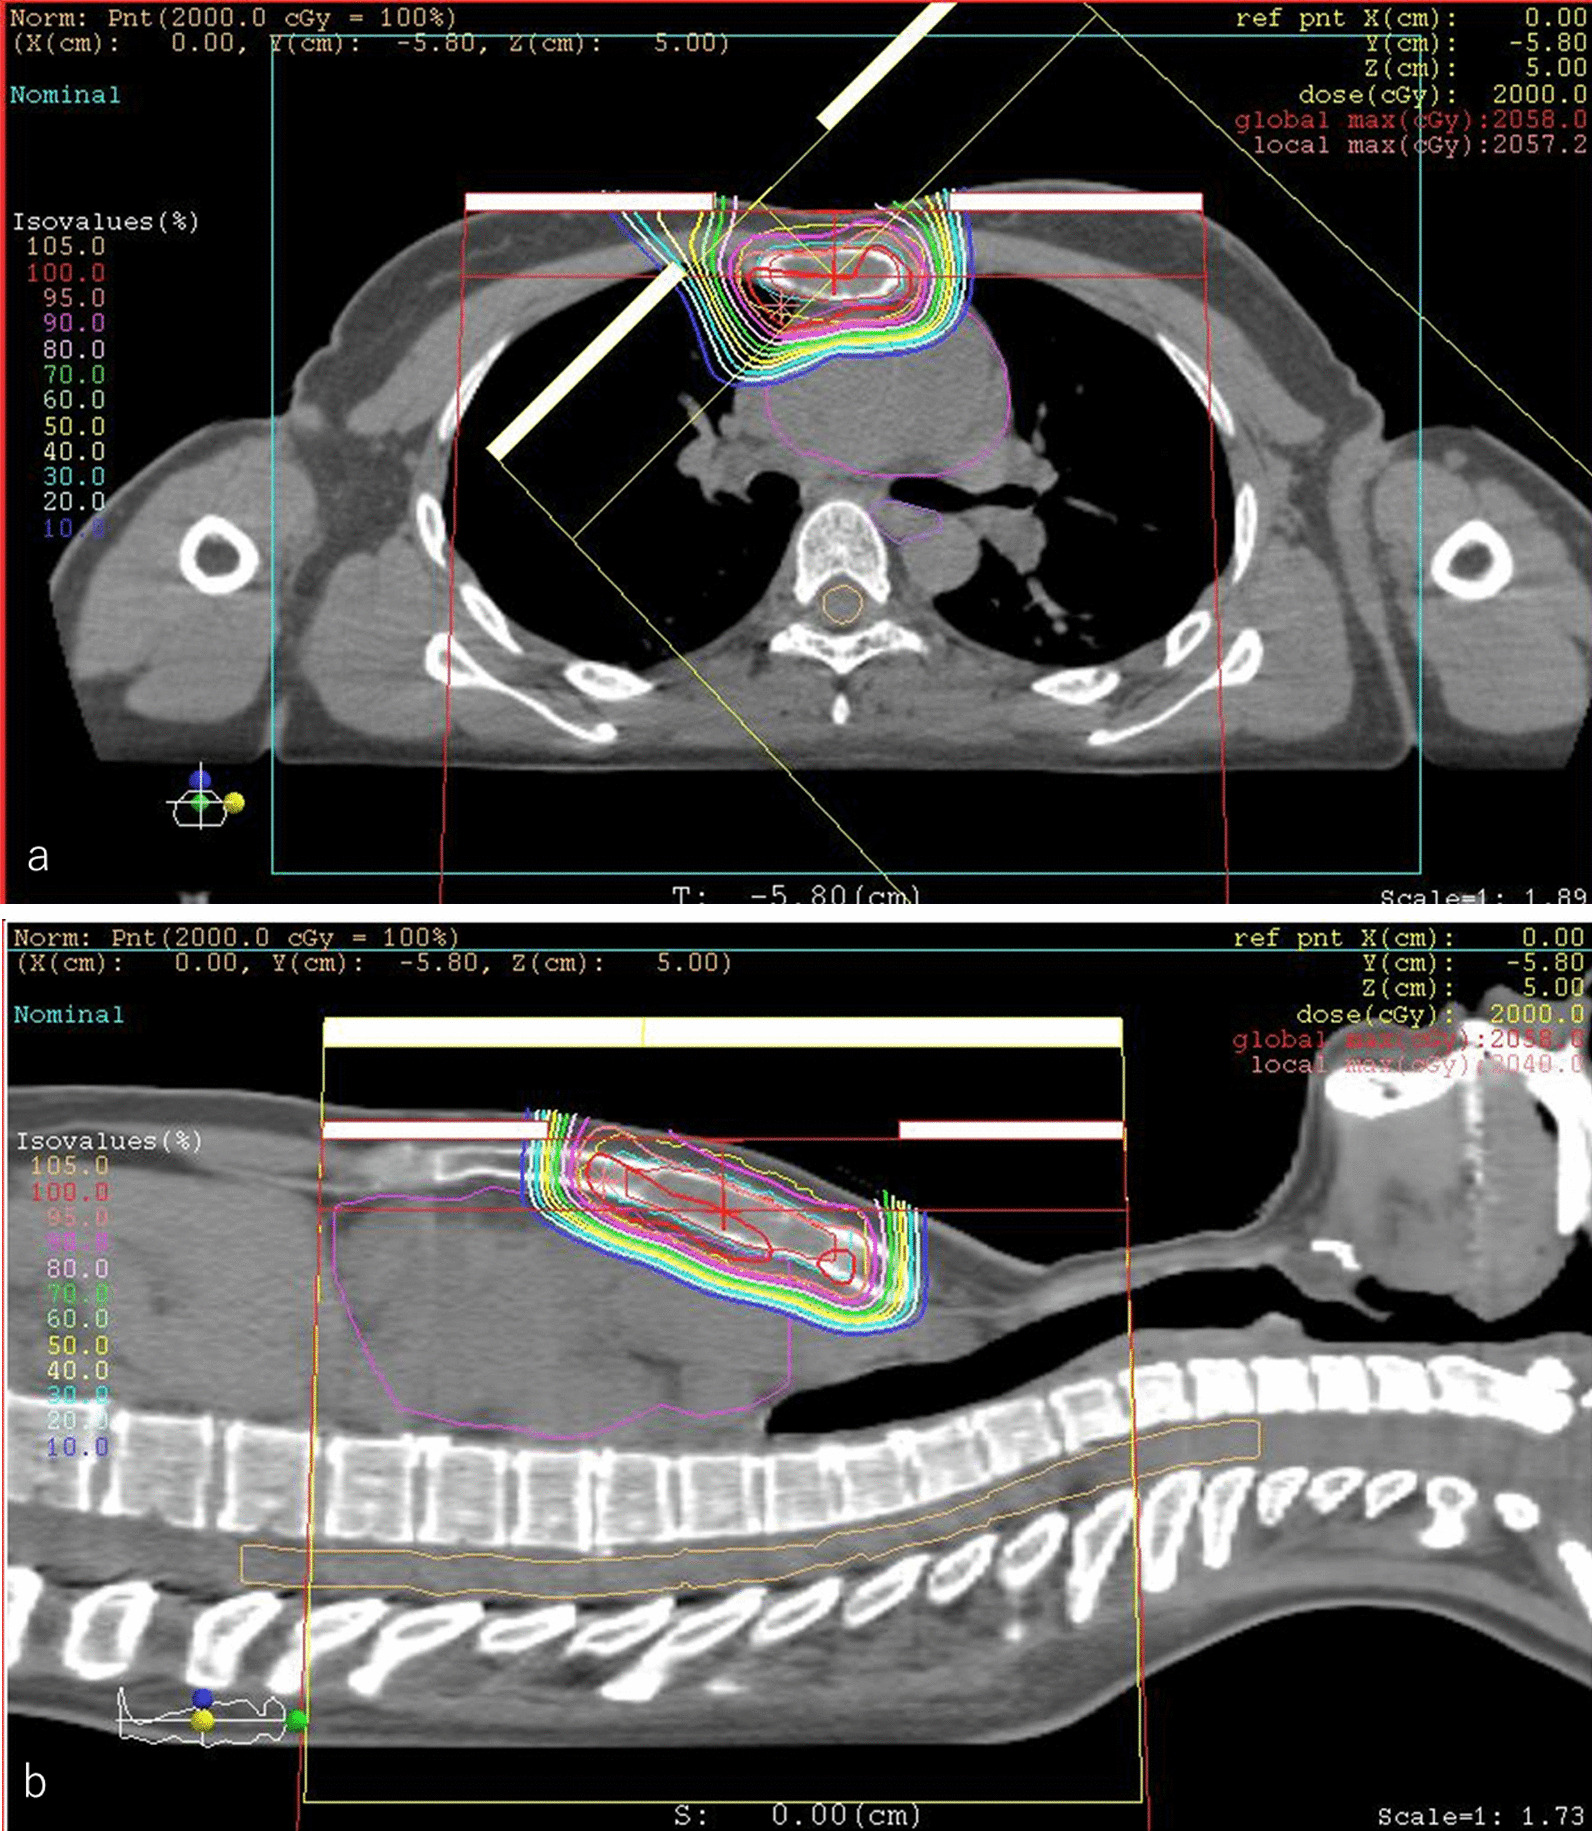

Fig. 4.

Dose distribution of boost proton beam therapy in an axial field (a) and a coronal field (b). The patient received 20 Gy relative biological effectiveness (RBE) in five fractions of a sequential boost for the sternal metastasis alone to a total dose of 70 Gy RBE. The gross tumor volume was 16.21 cm3. The clinical target volume was 29.89 cm3, and the planning target volume was 70.96 cm3